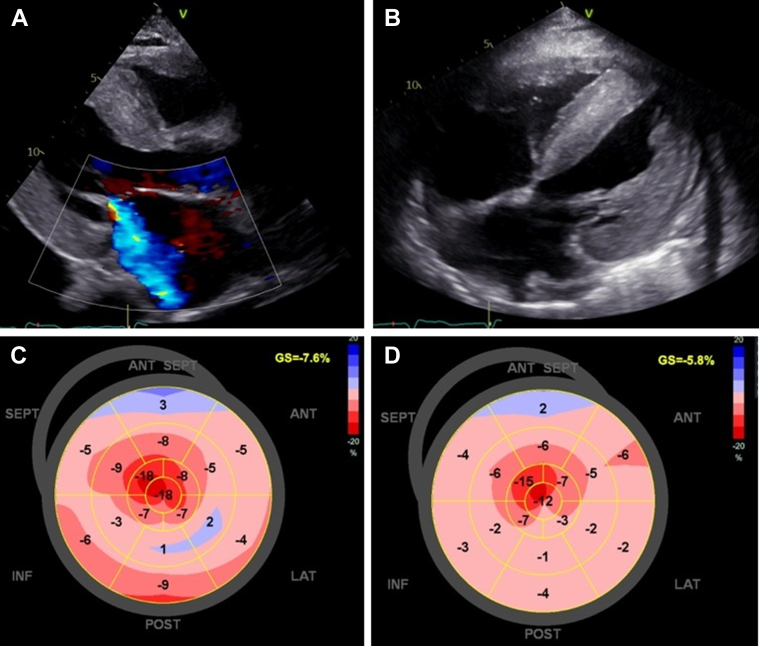

Figure 3.

Echocardiographic Image Documenting Disease Progression, With Marked Left Ventricular Hypertrophy

(A) Echocardiogram at 6 months after clinical presentation, showing severe concentric left ventricular hypertrophy and mitral regurgitation (long-axis view). (B) Echocardiogram at 8 months, demonstrating biventricular hypertrophy, interatrial septum hypertrophy, atrial enlargement, and findings concerning cardiac amyloidosis (4-chamber subcostal view). (C and D) Evolution of the bull's-eye plot pattern with further reduction in global longitudinal strain and the typical apical sparing pattern at 6 and 8 months after clinical presentation, respectively.

During the exhaustive clinical diagnostic process, the patient experienced multiple episodes of acute HF, leading to 4 hospitalizations with inadequate response to diuretic therapy. Although there is limited evidence from clinical trials, adjuvant therapy with doxycycline 100 mg once daily was initiated. However, no improvement in functional capacity or target organ response was observed, with severe left ventricular hypertrophy (IVS: 23 mm; posterior wall: 22 mm), significant biventricular dysfunction, pericardial and pleural effusion noted on transthoracic echocardiogram (Figures 3A to 3D), and a significant rise in cardiac biomarkers (N-terminal pro–B-type natriuretic peptide: 265,782 pg/mL and troponin T: 343 ng/L).